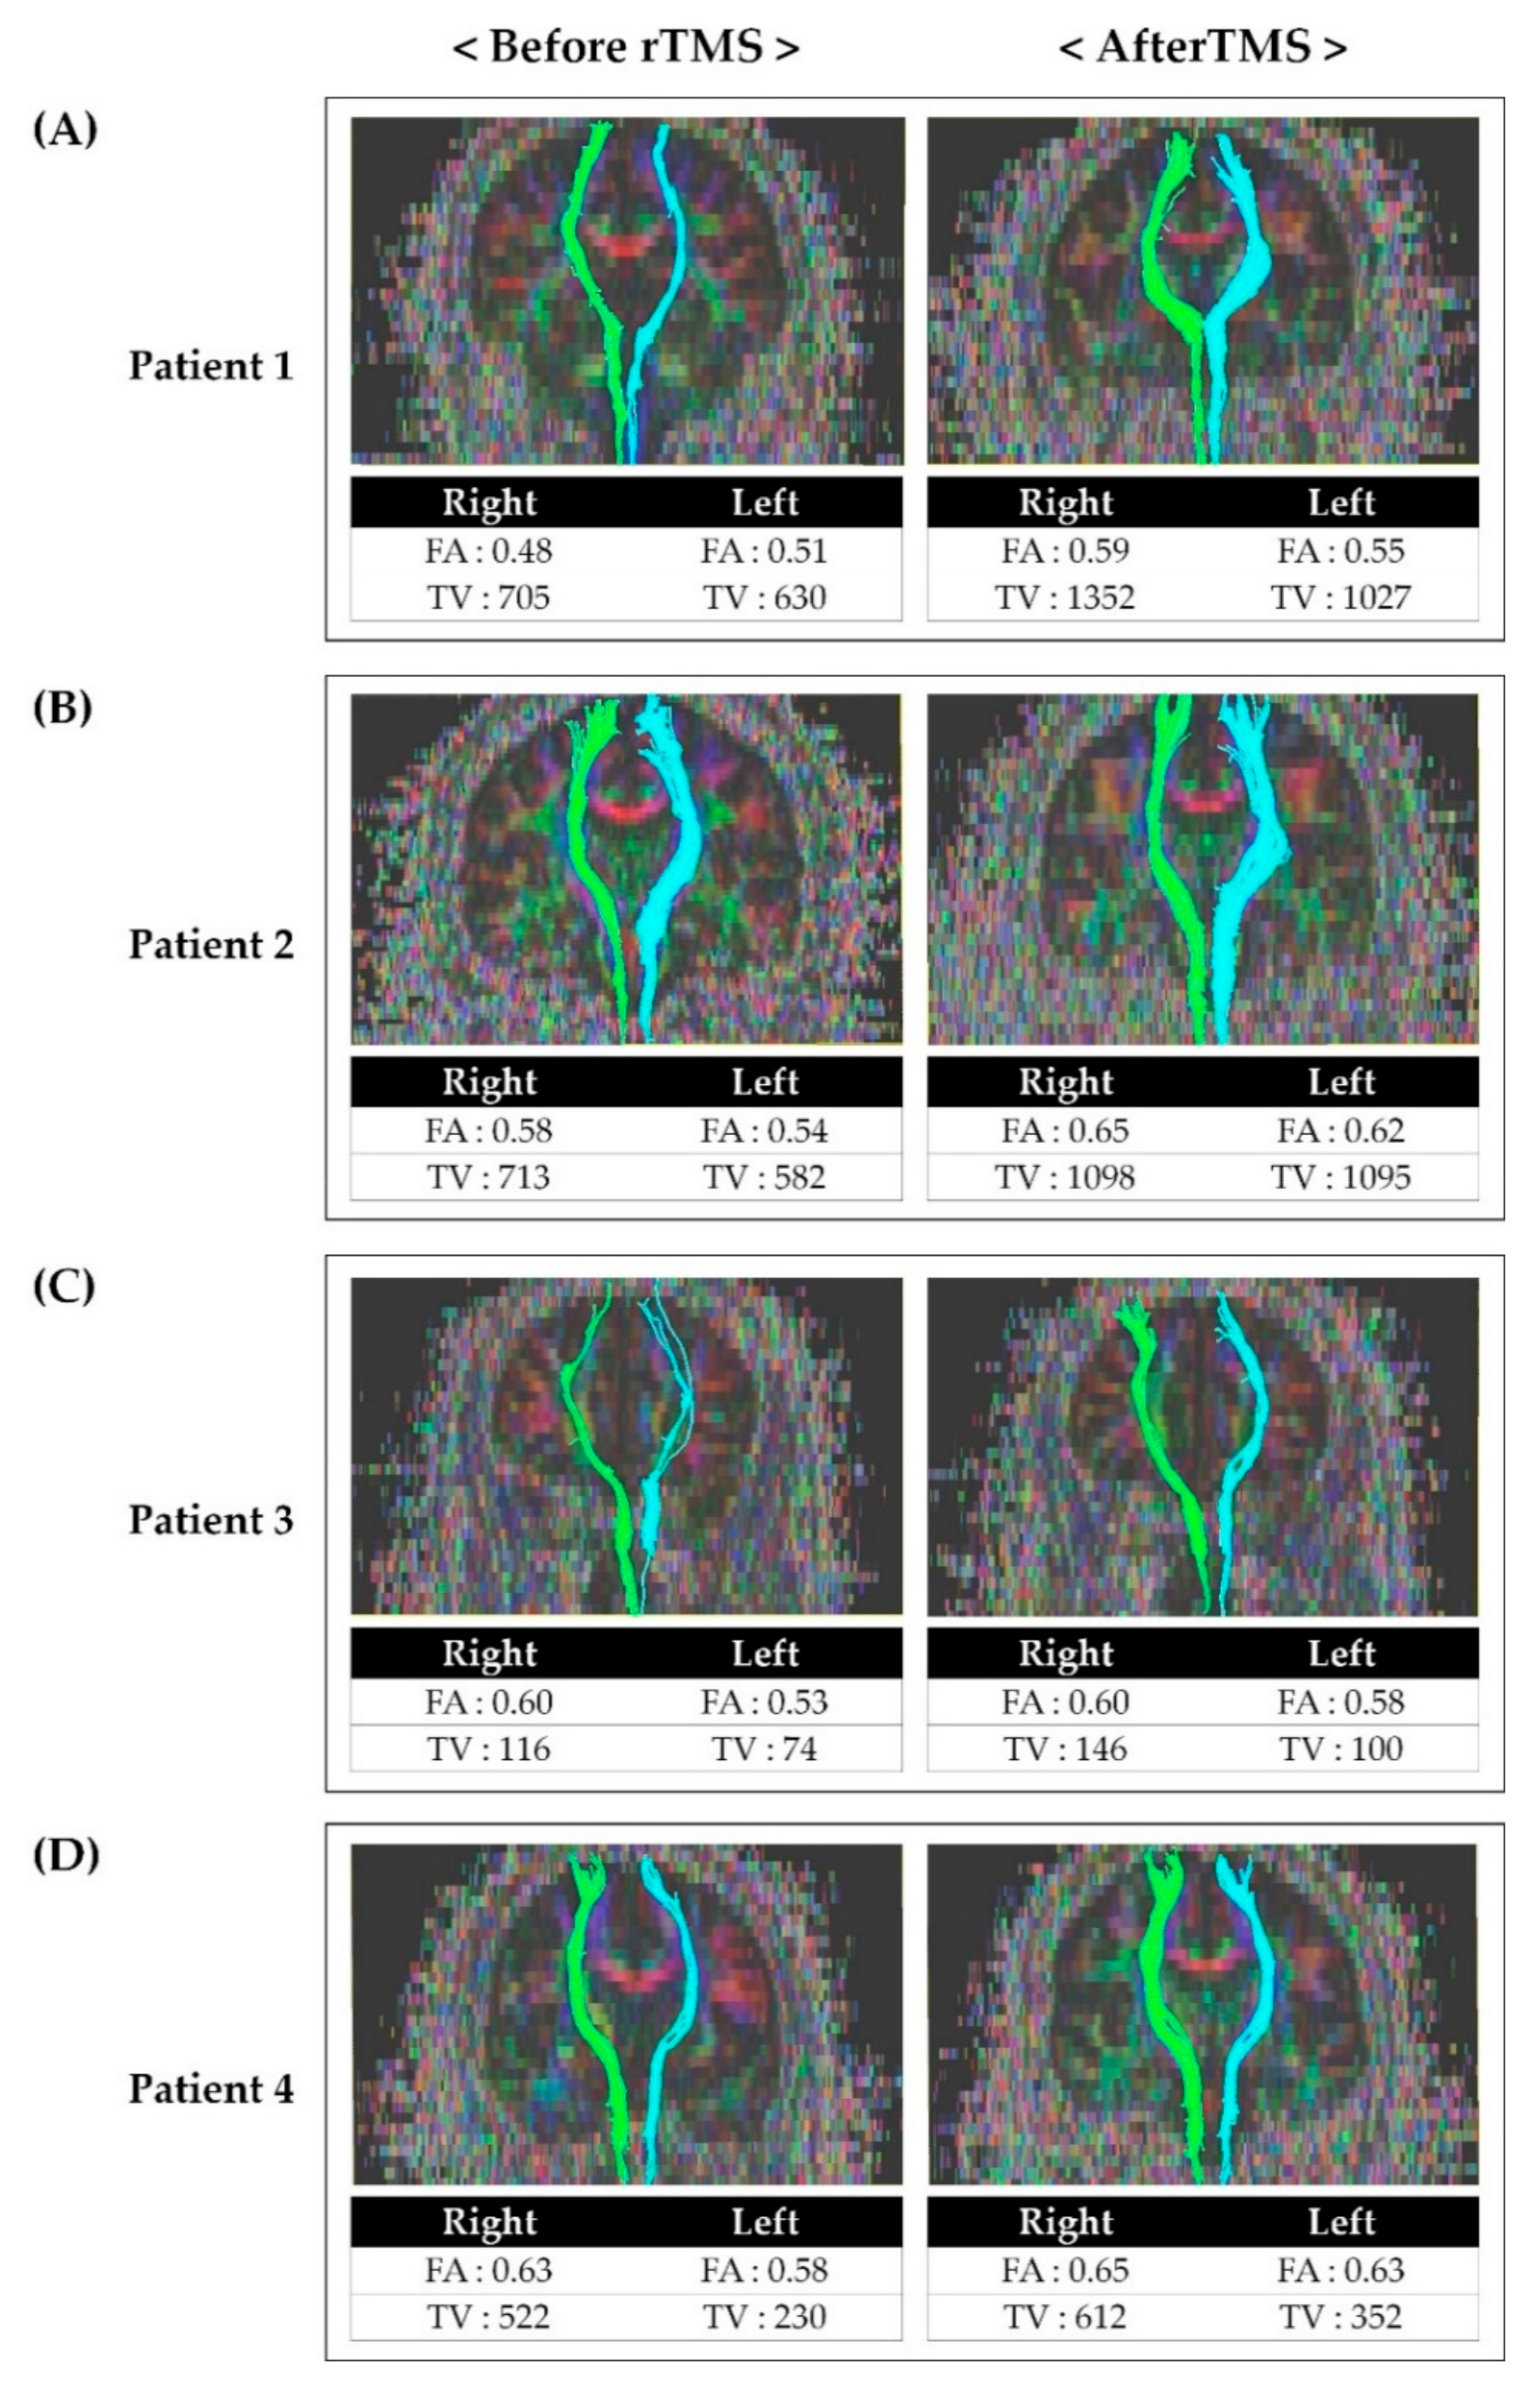

Before rTMS, the FA and TV values of the contralateral STT on the more painful side were generally lower than on the other side in all patients. The FA and TV values after rTMS was applied were increased compared to the results before rTMS (Figure 2).

Figure 2.

Tractography for the spinothalamic tract in patients before and after repetitive transcranial magnetic stimulation: (A) Tractography for STT in patient 1 before and after rTMS. (B) Tractography for STT in patient 2 before and after rTMS. (C) Tractography for STT in patient 3 before and after rTMS. (D) Tractography for STT in patient 4 before and after rTMS. After rTMS, FA and TV values had increased compared to the value before rTMS. Abbreviations: rTMS, repetitive transcranial magnetic stimulation; FA, fractional anisotropy; TV, tract volume; STT, spinothalamic tract.

Studies on the effect of rTMS on central pain and the association between central pain and STT have been reported. The mechanisms of rTMS to the motor cortex for neuropathic pain can be explained by a reduction in pain-related thalamic hyperactivity, regional cerebral blood flow changes, activation of descending pathways, and restoration of intracortical inhibition. However, consensus on the exact mechanism has not yet been achieved [5,10,31]. Although there are reports of the effect of rTMS on central pain, no studies have confirmed the effect of rTMS on central pain by comparing STT before and after rTMS. Therefore, assuming that pain reduction after rTMS may be related to the alleviation of STT problems, we performed follow-up DTI after rTMS (Figure 2). FA values indicate the directionality and integrity of white matter microstructures, and the reduced FA values are associated with impaired integration of the neural tract [18,20,32]. Moreover, the TV value represents the number of voxels included in the neural tract [32]. Therefore, lower FA and TV values more severe impairment of STT. After rTMS, it was observed that both FA and TV values had increased compared to those before rTMS. In addition, we also confirmed that the patients’ NRS and bedside sensory examination results improved as well. Considering the increase in FA and TV and improvement of symptoms after rTMS, rTMS is thought to have induced inhibition of hypersensitivity of STT and affected the integration of STT.